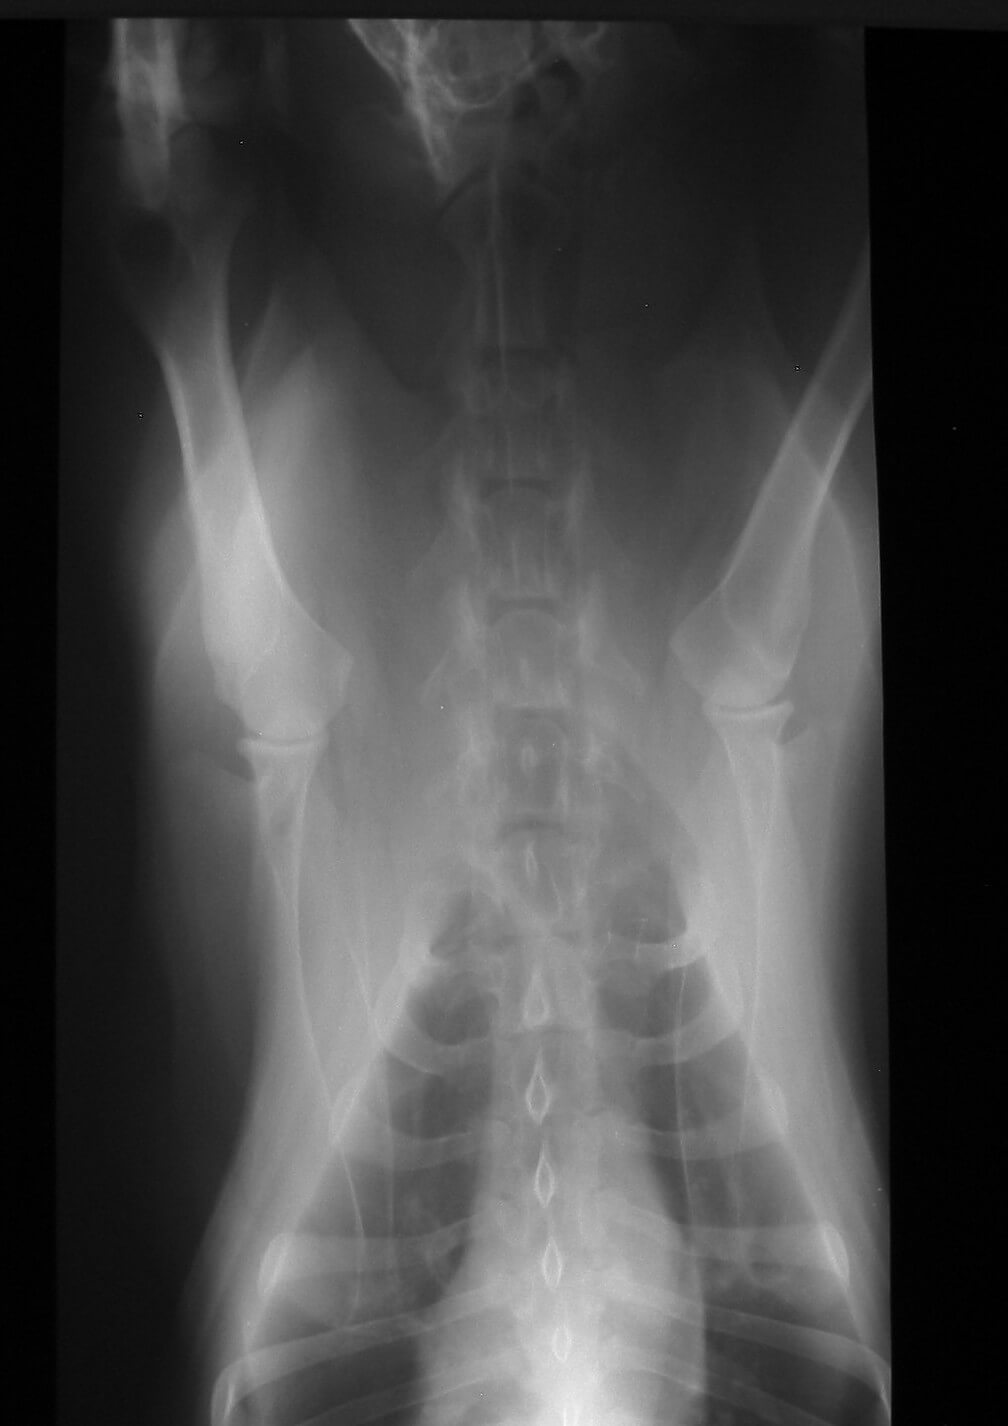

Radiology (X-rays)

Radiograph image

When we need to figure out what’s wrong with your pet, we routinely use x-rays to help identify the cause of the problem, rule out possible problems, or provide a list of possible causes. We may also use x-rays during a wellness exam to diagnose potential problems before they become serious.

X-rays provide valuable information about a pet’s bones, gastrointestinal tract (stomach, intestines, colon), respiratory tract (lungs), heart, and genitourinary system (bladder, prostate). We use radiology alone or in conjunction with other diagnostic tools. Interpretation of radiographs requires great skill on the part of the veterinarian.

We are proud to offer digital radiology (x-rays that are captured digitally rather than on film). This state-of-the-art technology allows us to provide you with a quicker diagnosis for your pet. Plus, it uses less radiation than traditional x-rays.

To avoid a blurry image, pets need to remain completely still while an x-ray is taken. In some cases, we may need to sedate your pet or use short-acting general anesthesia.